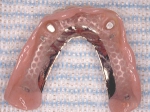

4本埋入終了4本埋入終了4本埋入終了(このシステムは4本が絶対条件) 義歯の調整義歯の調整当日に義歯の調整に取りかかる。裏側より義歯をくりぬき維持部のカバー(ハウジング)を義歯の内面に埋め込む step1 義歯の調整義歯の調整当日に義歯の調整に取りかかる。裏側より義歯をくりぬき維持部のカバー(ハウジング)を義歯の内面に埋め込む step2 義歯の調整当日に義歯の調整に取りかかる。裏側より義歯をくりぬき維持部のカバー(ハウジング)を義歯の内面に埋め込む step3

義歯の調整義歯の調整当日に義歯の調整に取りかかる。裏側より義歯をくりぬき維持部のカバー(ハウジング)を義歯の内面に埋め込む step4 義歯の調整義歯の調整当日に義歯の調整に取りかかる。裏側より義歯をくりぬき維持部のカバー(ハウジング)を義歯の内面に埋め込む step5 義歯の裏側義歯の裏側義歯の裏側 装着後しっかり噛める様になる